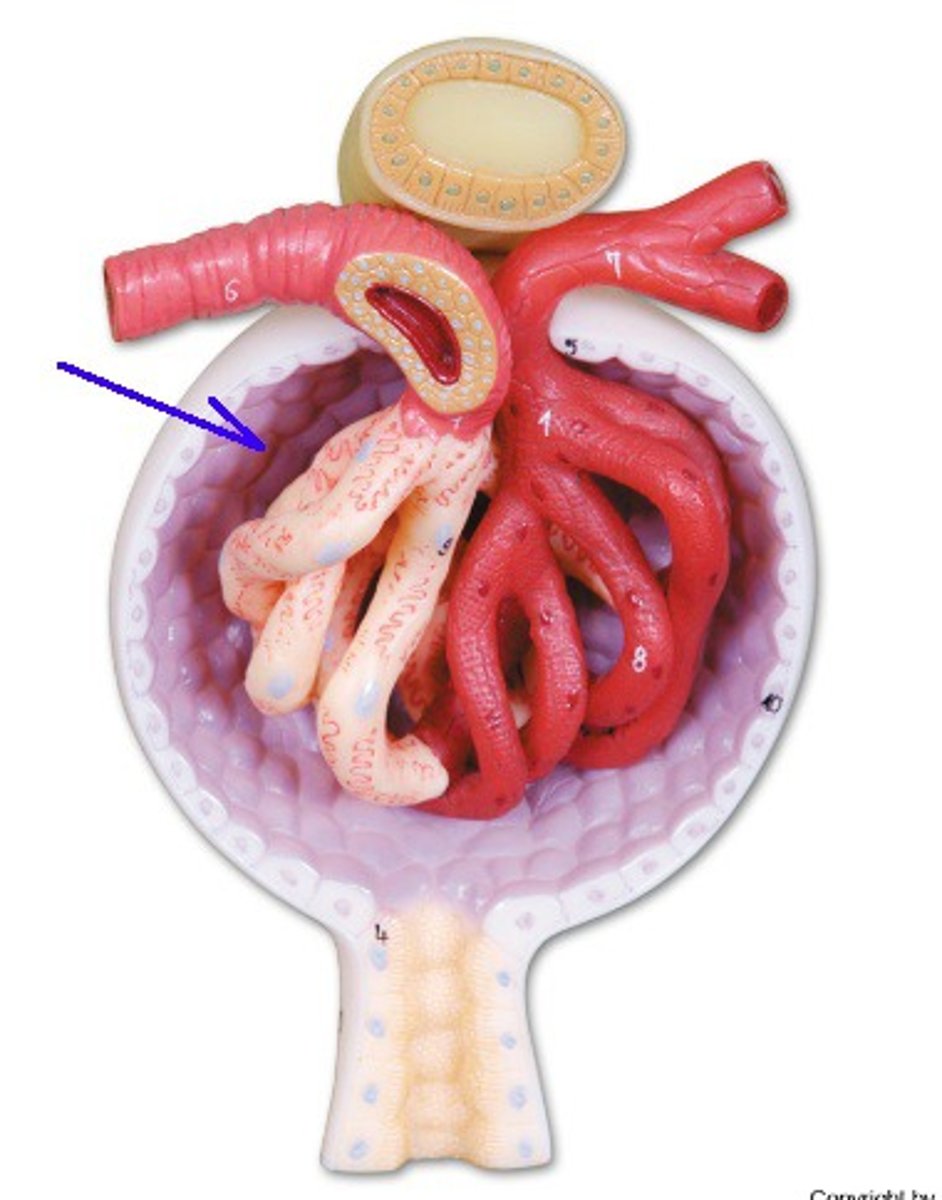

afferent arteriole

efferent arteriole

glomerulus

juxtaglomerular apparatus

Bowman's capsule / glomerular capsule

macula densa cells

juxtaglomerular cells

podocytes

capsular space

renal corpuscle

proximal convoluted tubule

distal convoluted tubule